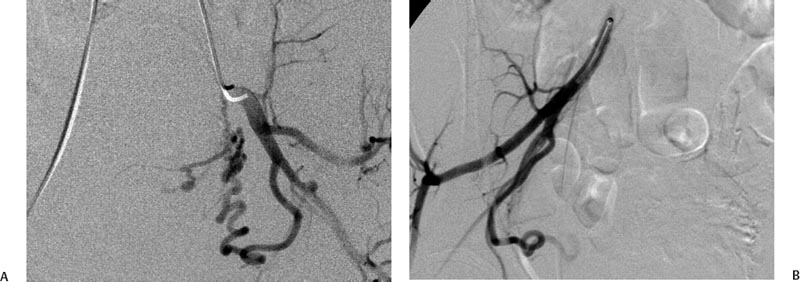

Хирургические процессы при эмболизации гемангиомы на фото